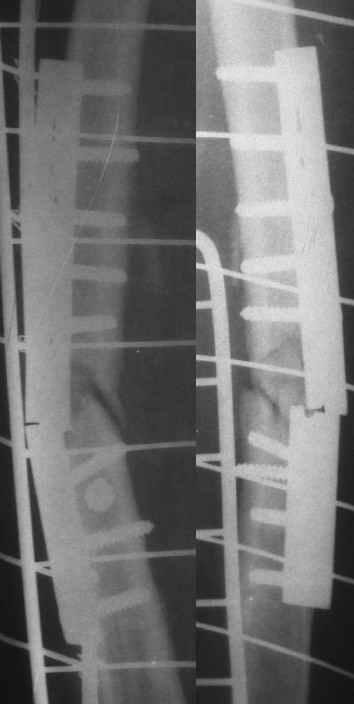

История болезни этой пациентки началась 5 лет назад с перелома бедра в ДТП, оперирована 2-ы пластиной накостно в одной из больниц нашего города, 2-ы перелом импланта, после последнего раза поступила в нашу клинику, где был выполнен блокированный остеосинтез. Через два года гвоздь удалён (по просьбе больной), Rg-сращение. Через год после удаления рефрактура от незначительной травмы, остеосинтез гвоздём с блок., в раннем послеоперац. периоде жировая эмболия, после купирования амбул. лечение. Прошу советов по дальнейшему лечению.

перелом пластины после I опер

перелом пластины после II опер

III опер.